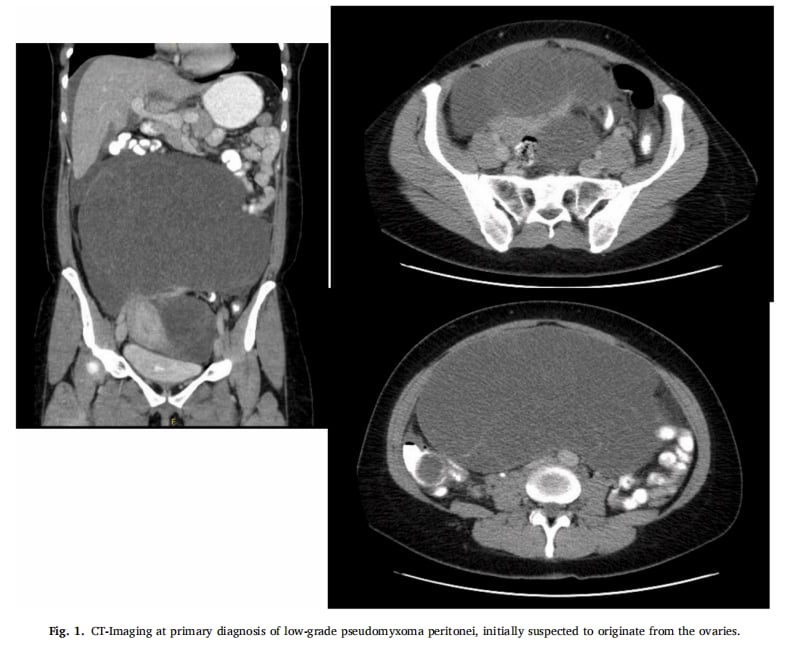

患者最初因巨大的黏液性肿瘤就诊,影像学检查(CT)一度怀疑是卵巢癌起源。探查性剖腹术证实肿瘤起源于阑尾,并已累及双侧卵巢,盆腔腹膜上可见多处胶状沉积物,确诊为PMP。患者接受了彻底的肿瘤细胞减灭术,包括回盲部切除术、双侧输卵管卵巢切除术、网膜切除术以及所有可见黏液斑块的切除。术后病理确认为LAMN伴低级别PMP,减瘤效果彻底。

▲图1 基于CT成像显示初步诊断低级别腹膜假性黏液瘤,最初怀疑其起源于卵巢